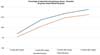

Both groups presented progressive reabsorption. ►Table 1 and ►Fig. 5 show the change in mean subcutaneous thickness in both groups.

In the decanted graft group, the average reduction compared with the initial thickness after lipofilling was 9.90% on day 15, 19.27% on month 1, 23.59% on month 3, and 26.36% on month 6. In the filtered graft group, the average reduction compared to the initial thickness after lipofilling was 7.74% on day 15, 14.85% on month 1, 20.67% on month 3, and 22.80% on month 6 (►Fig. 6). ►Figs 7–8 reveal the ultrasound change in subcutaneous tissue’s thickness before and after lipofilling. ►Figs. 9–10 show the pre-and postoperative results of one patient from each group.